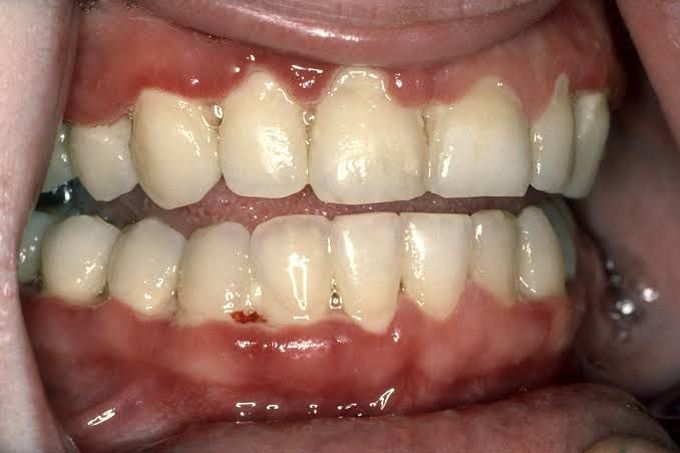

Acute necrotizing ulcerative gingivitis (ANUG) is a painful infection of the gums that causes fever, sometimes foul-smelling breath, and feeling ill. If the normal bacteria in the mouth overgrow, the gums can become infected. The gums hurt, and people sometimes have extremely bad breath.